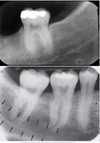

What radiopaque structure is represented in this picture?

External Oblique Ridge

What radiopaque structure is highlighted in this structure?

Internal Oblique Ridge

What structure is represented in this picture?

Mylohyoid Ridge